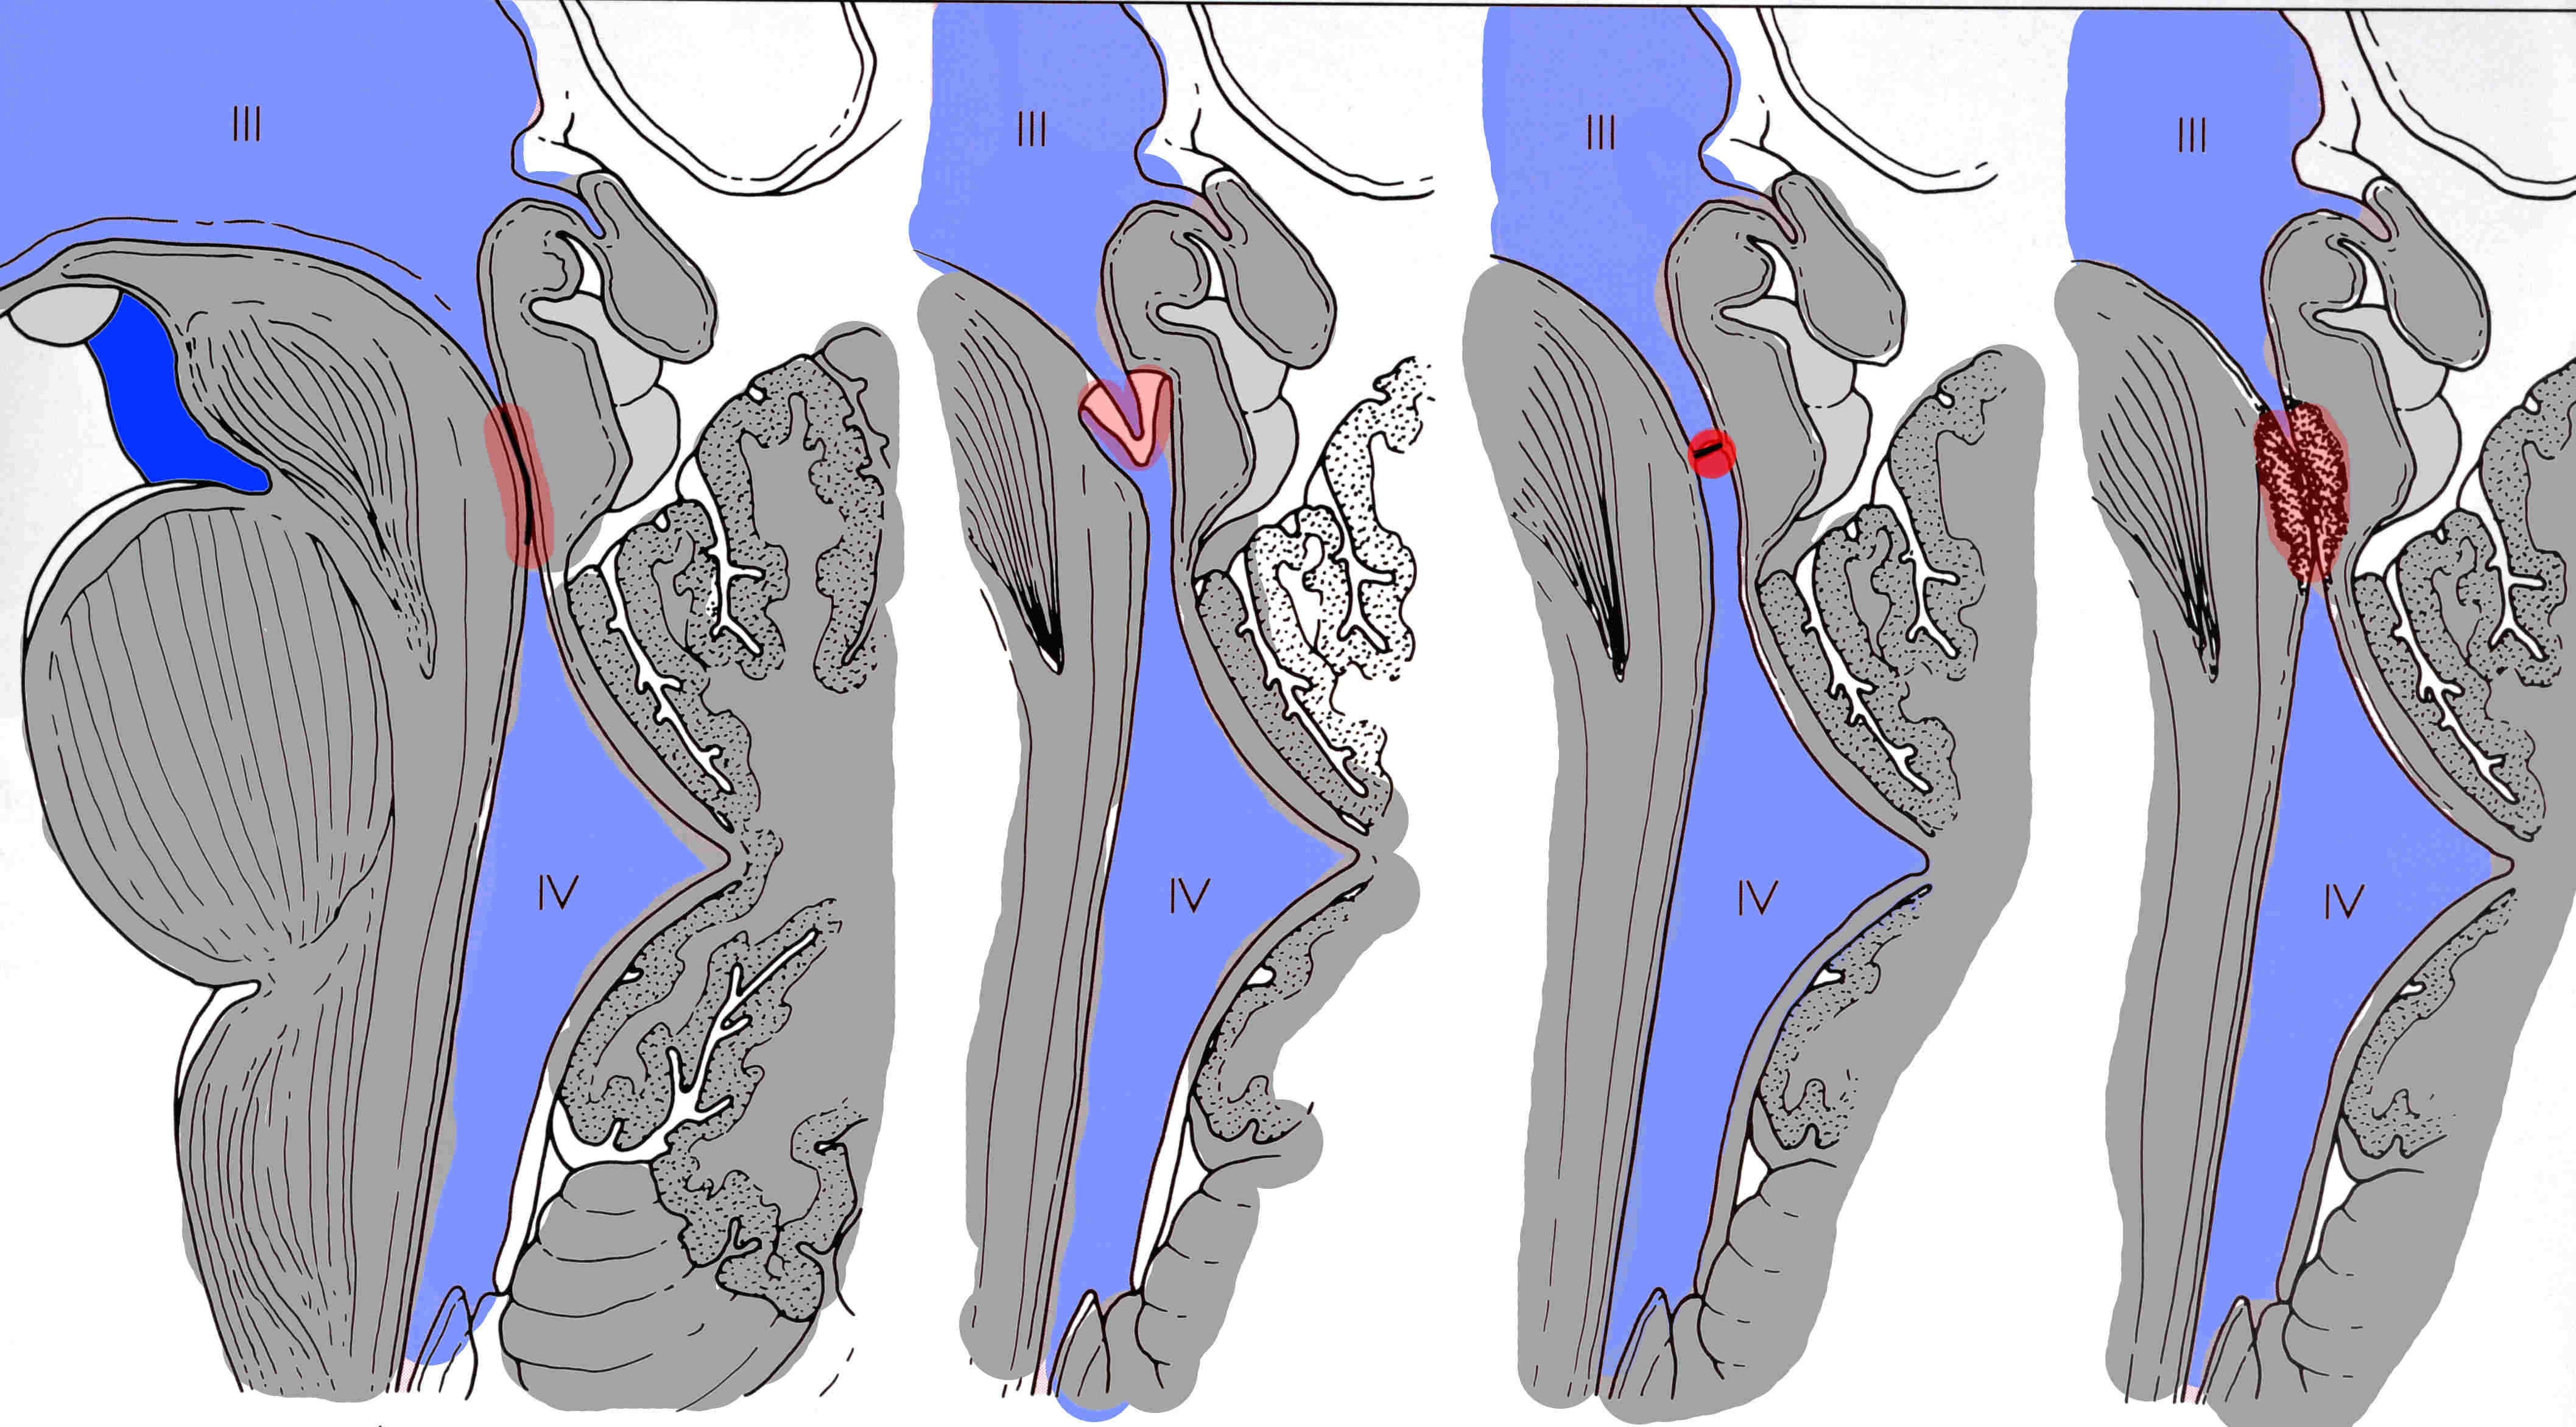

Die Aquäduktstenose ist zweifellos ein Okklusionshydrocephalus. Hierbei ist die Passage des Liquors vom III. Ventrikel zum IV. Ventrikel behindert. Der Verbindungskanal zwischen diesen Ventrikeln heißt Aquädukt. Er kann auf völlig unterschiedliche Weise verengt sein, wie die obige Abbildung zeigt. Die Ursachen sind vielfälltig: In 10% d.F. handelt es sich um eine genetisch vererbte Erkrankung. Hierbei fällt nur der normal 0,75 mm durchmessende Aquädukt enger aus als normal. Zu bedenken ist auch, dass dieses Krankheitsbild dann auf die Kinder des Betroffenen übergehen kann. Daneben können Hirnhautentzündungen, Hirnblutungen u.a. eine Aquäduktstenose verursachen. Besonders wichtig: Manchmal sind es Tumore, die den Aquädukt zupressen. Diese können manchmal primär so winzig sein, dass sie zwar die Aquäduktstenose verursachen, aber bestenfalls mit Mühe in sehr guten Kernspinuntersuchungen mit Kontrastmittel entdeckt werden. Patienten mit Aquäduktstenosen sollten auch nach Therapie des Hydrocephalus daher engmaschig nachuntersucht werden, damit ein wachsender Tumor nicht übersehen wird.

Aquäduktstenose

Es handelt sich dabei um eine Veränderung in der hinteren Schädelgrube, die durch folgende Merkmale charakterisiert ist: Der mittlere Teil des Kleinhirns (Kleinhirnwurm) ist unvollständig angelegt (Dysgenesie), dadurch kann sich der IV. Ventrikel in diesen Bereich, wo der Kleinhirnwurm fehlt, ausdehnen. Er ist quasi zystenartig ausgezogen. Hinzu kommt, dass zumindest eine der 3 Öffnungen des IV. Ventrikel, die den Liquor in die äußeren Liquorräume passieren lassen, verschlossen ist. Meist ist das so genannte For. Magendii betroffen, seltener die For. Luschkae. Somit entwickelt sich auch hieraus ein Okklusionshydrocephalus.

Als Dandy-Walker Variante bezeichnet man Veränderungen, die alle Charakteristika des Dandy-Walker Syndroms haben, nur dass ihnen die zum Syndrom gehörende Vergrößerung der hinteren Schädelgrube fehlt.